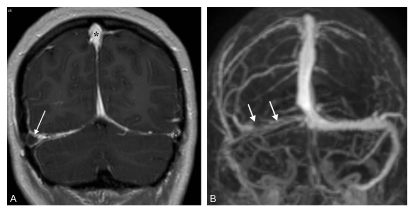

C. Thrombose veineuse cérébrale

En IRM, le sinus thrombosé apparaît en hypersignal sur les séquences pondérées en T1, en T2 et en FLAIR. Après injection de gadolinium, le rehaussement des parois dure-mériennes du sinus contraste avec le défaut d’opacification de sa lumière thrombosée (figure 50.5A) : c’est le signe du « delta vide ». En angiographie par résonance magnétique veineuse, les sinus perméables sont bien visibles alors qu’un sinus thrombosé n’est plus visible (figure 50.5B). En cas d’atteinte parenchymateuse apparaissent des lésions, le plus souvent cortico-sous-corticales, en hypersignal en T2/FLAIR, parfois hémorragiques.

Fig. 50.5 Thrombose du sinus latéral droit en IRM.

Coupe frontale pondérée en T1 avec injection (A) : opacification normale des sinus sagittal supérieur et latéral gauche (∗), défaut d’opacification du sinus latéral droit thrombosé (flèche), réalisant un signe du « delta vide ». L’angiographie par résonance magnétique veineuse (B) retrouve le défaut d’opacification du sinus latéral droit (flèches).

Source : CERF, CNEBMN, 2022.